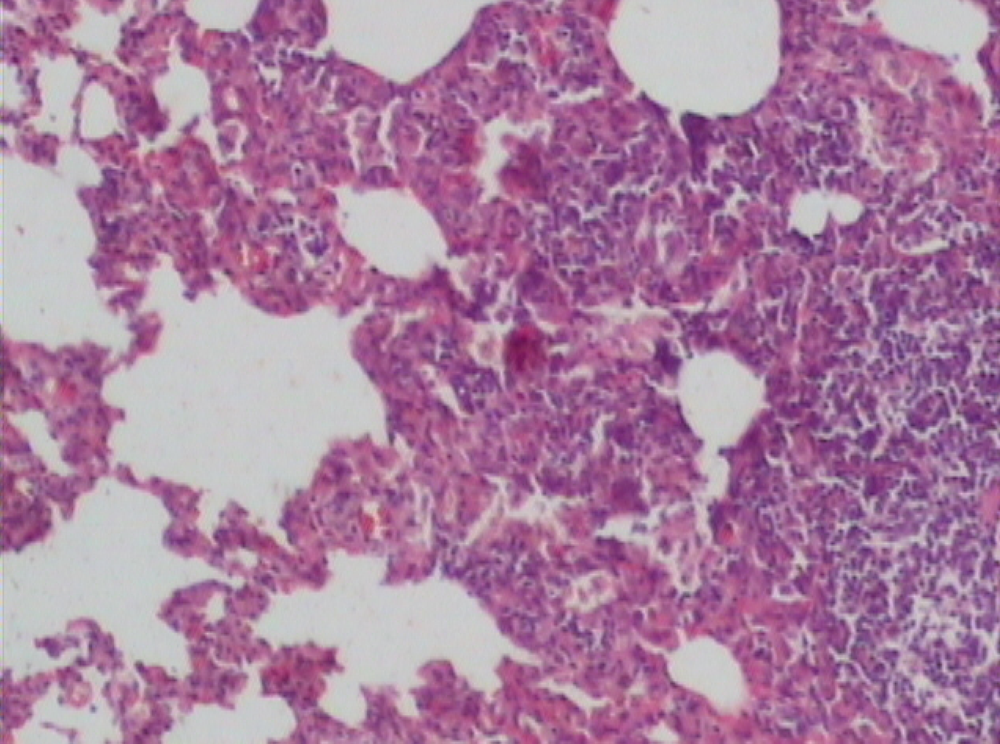

Supplementation of probiotics will effectively prevent neutrophil infiltration of the lung and also reduce the subsequent tissue destruction, as demonstrated in studies with inflammation induced by cecal ligation and puncture (CLP). A synbiotic formulation, Synbiotic 2000 Forte (see further below), was administered orally before the induced trauma and effectively prevented both neutrophil accumulation and tissue destruction in the lungs [50]. Most interestingly, these effects were obtained also when the LAB of the composition were injected subcutaneously (Figure 1,Figure 2,Figure 3) [51].

The average neutrophil count in the lungs (average of five fields) was: mixture of LAB and bioactive fibers 9.00 ± 0.44 (1), only LAB 8.40 ± 0.42 (2), only bioactive fibers 31.20 ± 0.98 (3), placebo (non-fermentable fiber) 51.10 ± 0.70 (4). The reduction of inflammation by the treatment was also demonstrated by significant reductions in myeloperoxidase (MPO), malondialdehyde (MDA), and nitric oxide (NO): MPO being 25.62 ± 2.19 (1), 26.75 ± 2.61 (2), 56.59 ± 1.73 (3), and 145.53 ± 7.53 (4) respectively (resp.), MDA 0.22 ± 1.31 (1), 0.28 ± 3.55 (2), 0.48 ± 5.32 (3) and 0.67 ± 2.94 (4) resp. and NO 17.16 ± 2.03 (1), 18.91 ± 2.24 (2), 47.71 ± 3.20 (3) and 66.22 ± 5.92 (4) resp.—all differences being statistically significant (>0.05).

Figure 2.

Synbiotic treated group.